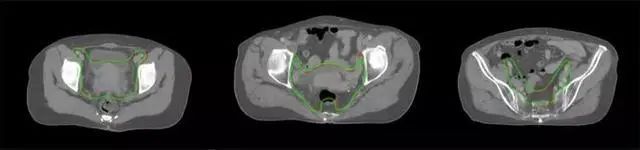

四、放射治療智能勾畫(huà)軟件

產(chǎn)品背景

放射治療,簡(jiǎn)稱(chēng)放療,是治療腫瘤主要手段之一,利用放射線破壞照射區(qū)(靶區(qū))的細(xì)胞,使腫瘤細(xì)胞停止分裂直至死亡,醫(yī)生通常把放射治療形象的比喻為“打靶”,放療前精準(zhǔn)勾畫(huà)腫瘤靶區(qū)范圍是腫瘤放射治療的關(guān)鍵步驟。傳統(tǒng)的靶區(qū)勾畫(huà)醫(yī)生會(huì)根據(jù)患者多張CT、MRI影像片憑借經(jīng)驗(yàn)進(jìn)行,比較耗時(shí),治療的病人數(shù)量也有限,且靶區(qū)勾畫(huà)缺少行業(yè)統(tǒng)一的規(guī)范和標(biāo)準(zhǔn),無(wú)法達(dá)到同質(zhì)化,勾畫(huà)精確度不理想。

技術(shù)原理

基于深度學(xué)習(xí)人工智能的放療靶區(qū)智能勾畫(huà)技術(shù)和自動(dòng)計(jì)劃技術(shù),基于全面的市場(chǎng)調(diào)研和臨床專(zhuān)業(yè)意見(jiàn),采用獨(dú)創(chuàng)的基于小樣本量的人工智能算法,實(shí)現(xiàn)放療靶區(qū)和危及器官的快速全自動(dòng)勾畫(huà)。

產(chǎn)品優(yōu)勢(shì)

縮短至幾分鐘內(nèi)便可完成,大幅提升了放療效率,且人工智能平臺(tái)完成的靶區(qū)勾畫(huà)可基本滿足臨床醫(yī)生需求,專(zhuān)家只需審核時(shí)細(xì)微調(diào)整,可顯著提高靶區(qū)勾畫(huà)的規(guī)范化及精準(zhǔn)度,讓放療智能化,標(biāo)準(zhǔn)化。可覆蓋食管癌、鼻咽癌、直腸癌、宮頸癌、肺癌等多種病種。